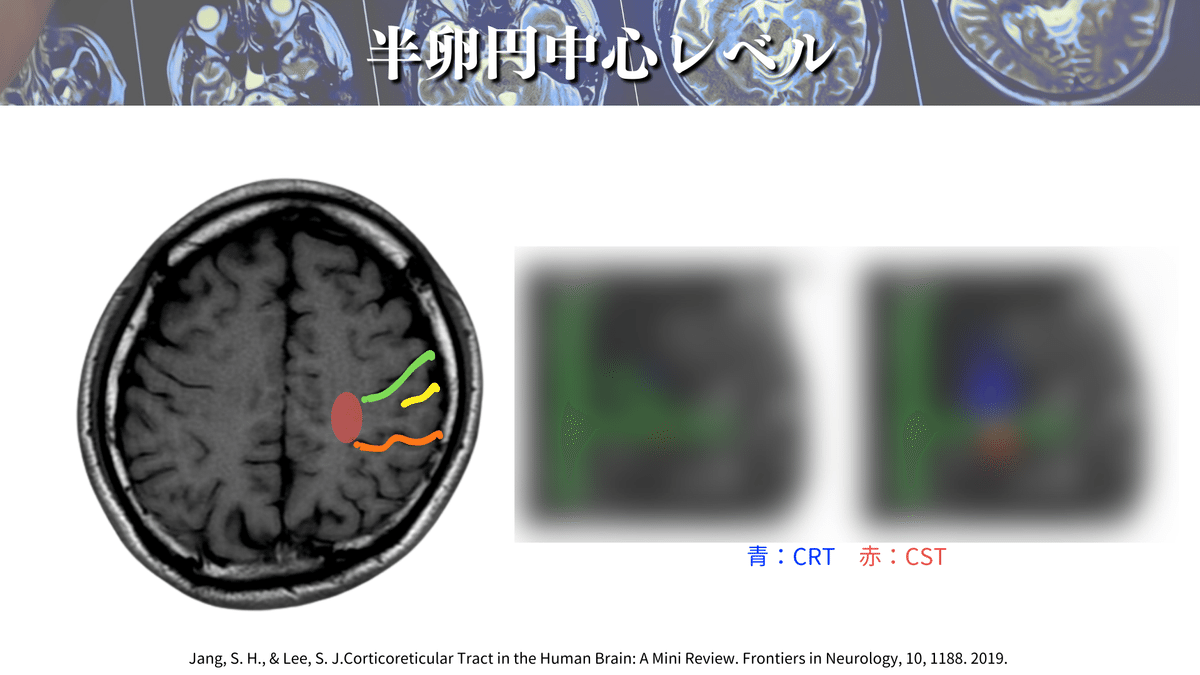

まずは大まかな場所を押さえましょう!

上図のように大体この辺りをCSTは通過していきます👍

そして、さらに解像度を上げると、、、🔍

こんな感じになります!(上図)

このレベルでは口顔👄の効果器特異的領域も見えてくるかもしれません!